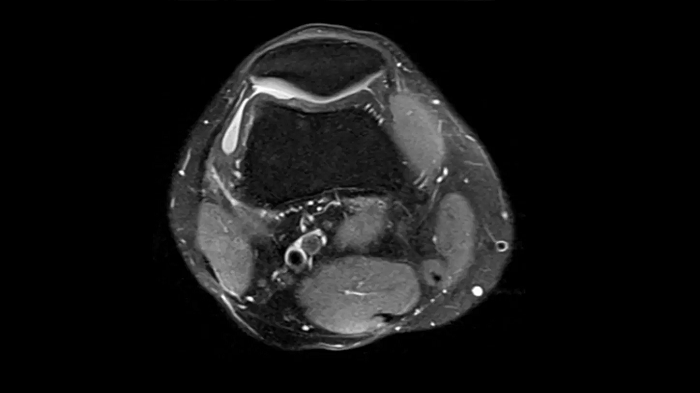

Knee

PD TSE Fat Sat with Deep Resolve and Simultaneous Multi-Slice

For clear imaging of the knee, outstanding fat suppression and performance are possible. Integrating the influence of Deep Resolve with the established Simultaneous Multi-Slice technique.

SMS 2 | Deep Resolve Gain & Sharp

0.4 x 0.4 x 3.0 mm2

TA 2:56 minutes

MAC-ID: 7aaaa0198.

MAC-ID: 7aaaa0198. Image Credit: Siemens Healthineers